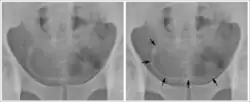

- Cystite et urétérite (S. haematobium) avec hématurie, qui peut évoluer en cancer de la vessie (carcinome épidermoïde) ;